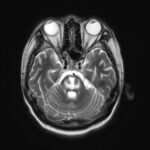

A jaundiced 36 year old develops spastic quadriplegia

A 36 year old alcoholic man was admitted to hospital with obtunding, jaundice and cachexia. In addition to deranged LFTs, anaemia and thrombocytopenia, all thought to be related to cirrhosis, he had Creat 194 (eGFR 36), Na 138, K 2.6. … Continue reading →

Posted in Metabolic, Neurology | Tagged Level B